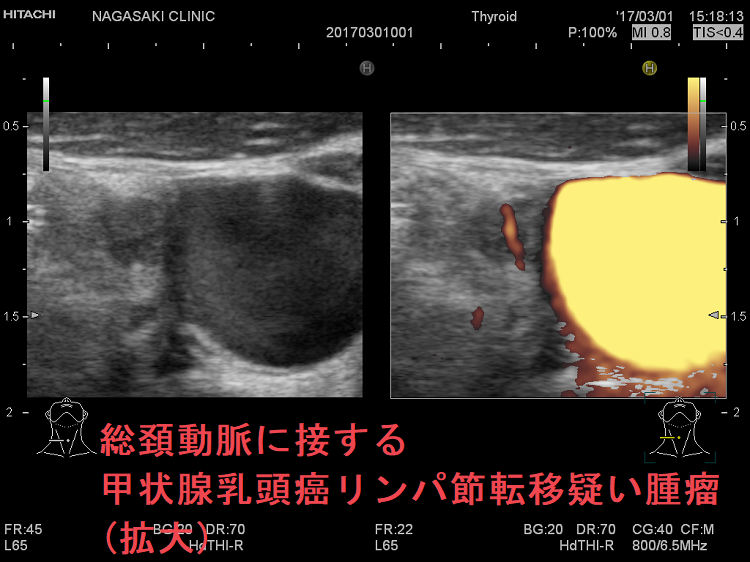

- 頚動脈に接する小さな甲状腺腫瘍

- 頚動脈近傍で、頸動脈に連鎖して拍動する小さな甲状腺腫瘍

甲状腺乳頭癌の可能性があるため、穿刺細胞診したくても、頚動脈や気管を刺してしまう危険を考えれば断念するのが正しいと思います。「退く勇気」も大切なのです。その代わり、甲状腺腫瘍が大きくならないか、腫瘍マーカーは上昇しないか、定期的に経過を見る必要があります。

総頚動脈に接する甲状腺乳頭癌リンパ節再発